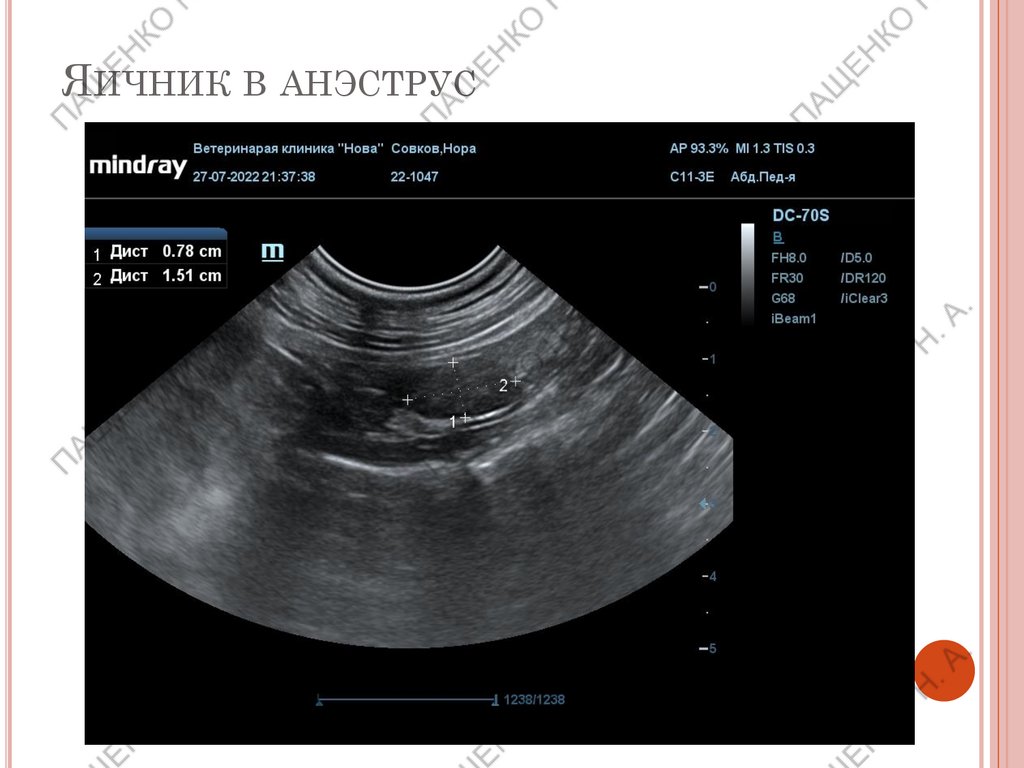

ЯИЧНИК В АНЭСТРУС

В анэструс размер до 1,2 см, овальные, с ровными контурами,

однородные.